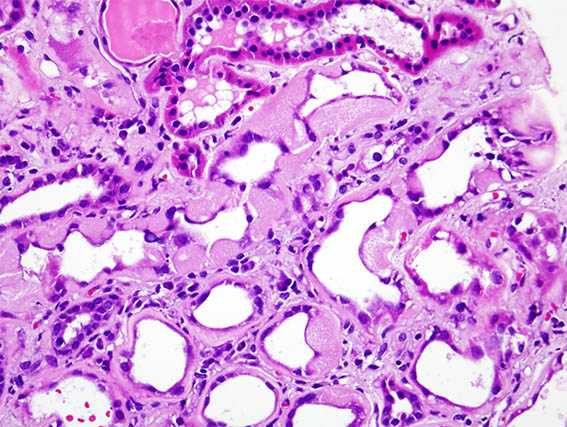

Una paciente de 41 años con diabetes mellitus de larga evolución desarrolló síndrome nefrótico abrupto, por lo que se le realizó una biopsia renal. La biopsia muestra nefropatía diabética avanzada sin GN superpuesta.

En una zona se identificaron lesiones tubulares como las que se ven en las siguientes imágenes:

Figura 1. H&E, X400. Note el material que hay en algunos túbulos.